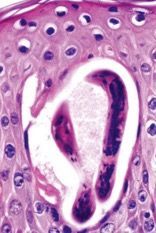

| Dermatophytes invade.. | skin, hair & nails – keratinophilic & keratinolytic Primarily involve stratum corneum |

| Dermatophytes H&E biopsy | |